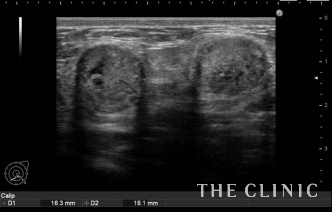

エコー検査では、両方のバストに多数のしこりを確認。超音波を反射しそれより内部が黒くなりなっていることから、しこりの辺縁には石灰化が認められます。

しこりはベイザーリポ(ベイザー脂肪吸引)の特殊な超音波で崩し、吸引針で穿刺することで除去しました。こちらの画像のように、エコーに映し出される映像を確認しながら行うことで、しこりに的確に吸引針を挿入することができます。